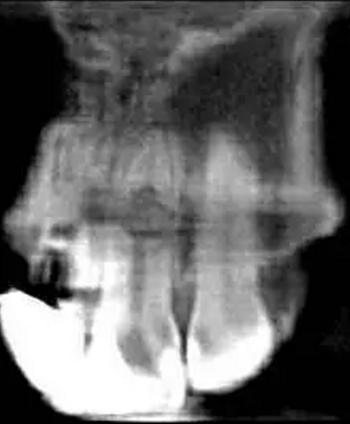

左上中切牙近遠中有牙色充填體,邊緣繼發齲,牙齒不松動,輕微叩痛,患牙冷測遲鈍,牙齦未見異常。X線片示:充填體周圍繼發齲壞近髓,根中部大面積低密度影,蟲噬狀,內部結構顯示不清晰,根尖周未見異常。錐形束CT(CBCT)顯示根中部內吸收多處可疑穿孔,缺損內可見菜花狀鈣化物影像